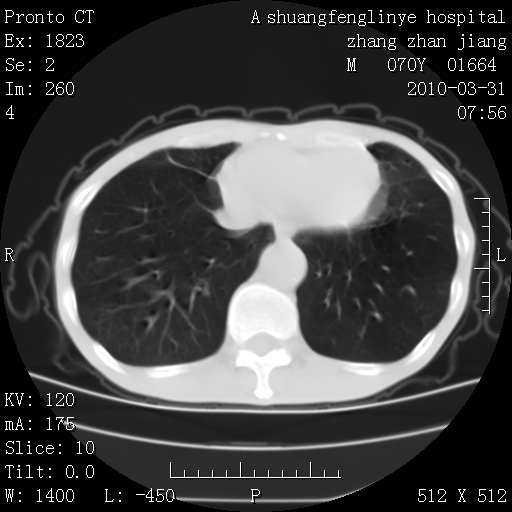

双上肺继发型tb并左上空洞形成,主动脉冠脉钙化。

1)两肺上叶继发性肺结核并左肺上叶空洞形成。2)冠状动脉及主动脉钙化。